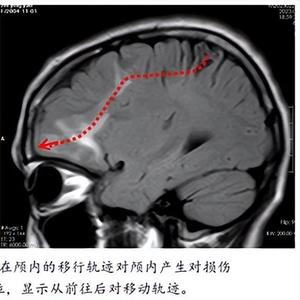

明确诊断后,需要进一步精准定位活虫在颅内的位置,因为颅内的多发脑软化灶是虫体在颅内的移动轨迹,通过间隔2周的薄层磁共振增强扫描,精准定位到寄生虫位置(左侧额叶前部)后,2月21日,陈俊喜带领团队为患者实施寄生虫抓取及肉芽肿切除术,最终从患者颅内顺利“活捉”一条长11厘米的裂头蚴,连同“虫窝”也一并切除了。

据彤彤回忆,她自幼生活在农村,小时候不懂事,渴了就直接喝井水、生水。“未经处理的水源,存在寄生虫或虫卵的可能性较大。”寄生虫及虫卵可以通过胃肠道进入血液,然后经血液循环进入大脑,在颅内移动过程中对颅脑产生损伤进而导致患者出现癫痫发作、肢体无力等系列症状。